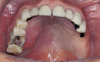

Was haben wir denn hier schönes?

Konservative Behandlung von Frakturen –> direkte Schienung —-> DRAHTBOGEN KUNSTSTOFFSCHIENE NACH SCHUCHARDT

Was ist das

Draht-Bogen-Kunststoff-Schiene nach Schuchardt, direkte Schienung (unter konservative Behandlung von Frakturen)